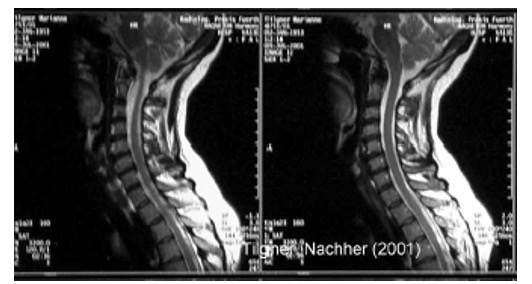

Эффективность лечения оценивалась по данным клинического наблюдения, показаниям электрофизиологических исследований: рентгенографии (включая рентгенографическую компьютерную томографию и магнитно-резонансную томографию (рис. 21а, 21б, 22а, 22б)), параметрам функции внешнего дыхания, показателям гемодинамики при реоэнцефалографии и лазерной допплерографии, компьютерно-оптической топографии позвоночника, электроэнцефалографии, результатам измерения величины электрокожного сопротивления в репрезентативных точках акупунктуры, стабилометрии и др. У всех пациентов независимо от основной патологии при мануальном обследовании выявлены функциональные блокады ПДС, напряжение различных групп мышц (прежде всего в мышцах верхнего плечевого пояса) и наличие в них болевых точек. Выраженность болевого синдрома оценивали по визуально-аналоговой шкале (ВАШ), выраженность тревожной и депрессивной симптоматики определяли по шкале А. Бека.

Рис. 22. Магнитно-резонансная томограмма шейного отдела позвоночника при болевом синдроме

а) ДО проведения Детензор-терапии отмечается секвестрированная грыжа межпозвонкового диска с компрессией дурального мешка

б) ПОСЛЕ проведения Детензор-терапии отмечается очевидный регресс грыжи межпозвонкового диска